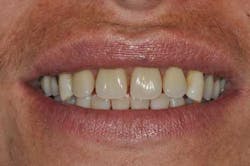

Figs. 8a, b, c, and d: Final results

- Final result.